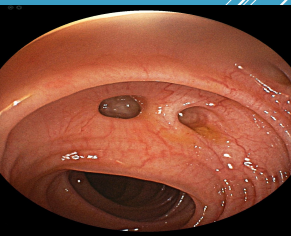

anywhere, left, sigmoid

Diverticular Disease

-Can occur ____________ in GI tract

-____ colon most common in Western countries (_______ most common)

-Right colon most common in Asian countries

-Small intestines is very rare